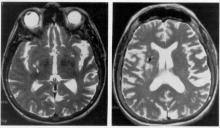

Anosognosia: Can You Treat Someone Who Doesn’t Accept They Are Ill?

The idea that some people with mental illness lack insight into their condition isn't new. And the condition, which health officials continue to grapple with, can also cause great stress for the loved ones of those afflicted by it.